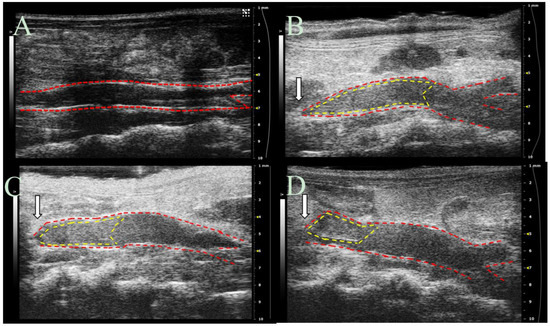

2.5. DVT Mouse Model

To assess the effects of DS-IEL30 in vivo, a study utilizing a mouse model of DVT was conducted. Partial ligation of the inferior vena cava (IVC) was performed and tail vein injections of saline (n = 6), 200 IU/kg heparin (n = 6), or 30 µM DS-IEL30 (n = 4) were administered. Ultrasound images were obtained at 6 h post-ligation for each mouse (Figure 9). The thrombus volume (expressed as mean ± standard error of the mean) was 12.3 ± 1.6 mm3 for saline, 5.0 ± 2.2 mm3 for heparin, and 4.3 ± 2.2 mm3 for DS-IEL30. The mean thrombus percentage (defined as thrombus volume/total IVC volume between the ligation suture and iliac bifurcation) was 63% ± 5% for saline, 26% ± 11% for heparin, and 26% ± 11% for DS-IEL30 (Figure 10). Both heparin and DS-IEL30 significantly decreased thrombus percentage compared to the saline controls (p < 0.05).

4.11. Ultrasound Imaging

Mice were anesthetized using 2%–3% isoflurane in 1.5 L/min oxygen. Cardiac and respiration rates were noninvasively monitored using gold-plated stage electrodes as part of the Vevo imaging station (FUJIFILM VisualSonics Inc., Toronto, ON, Canada). The mice were placed in a supine position on heated animal stage and the temperature was monitored using a rectal probe such that animals remained near 37°C. Depilatory cream was applied to remove hair on the abdomen prior to imaging, and warm ultrasound gel was applied on the skin to the entire abdomen just below the xiphoid process. IVC images were obtained using a Vevo2100 ultrasound imaging system with MS550D (40 MHz center frequency) and MS700 (50 MHz center frequency) transducers (FUJIFILM VisualSonics). The transducers were locked in the adjustable arm of the Vevo integrated rail system (FUJIFILM VisualSonics) for consistent image collection. In order to prevent distortion of the IVC, minimal pressure was applied to the abdomen to maintain original diameter of the vessel. The walls of the IVC were visualized with both long and short axes views. The angle of the stage was adjusted to optimize the view of the IVC and to minimize artifacts due to air and gas. Long and short axis B-mode images of the IVC were acquired at baseline (pre-operation) and at 6 h post-ligation of the IVC. Color Doppler images were used to assess blood flow through the IVC and branching vessels, and 3D scans of sequential slices were used to obtain vessel volumes as described previously [59,60] . Suture placement and the bifurcation of the IVC were used as landmarks to ensure consistent measurements between mice.

4.12. Ultrasound Image Analysis

All vessel measurements were made by the same ultrasonographer using Vevo LAB software (FUJIFILM VisualSonics). Thrombus length and volume and vessel volume were calculated using both the long axis and short axis ultrasound images. To determine the location of the thrombus, Color Doppler flow and B-mode images were utilized to visualize blood flow. The thrombus was also visualized as a hyperechoic region within the vessel lumen. Thrombus length was determined from the suture (point of IVC partial ligation) to the farthest point of thrombus and was calculated using an average of five measurements per image. The length of the thrombus in the 3D scans was compared to the length of thrombus in the long axis B-mode to ensure agreement. Thrombus volume was calculated by lofting together individual 2D segmentations from the first hyperechoic region in the lumen to the suture (where the lumen signal changed from hyperechoic to hypoechoic). Total IVC vessel volume was obtained using these same volumetric images and was measured from the suture to the IVC bifurcation. Percentage of IVC occlusion was obtained by determining the amount of thrombus volume within the total volume of the vessel.

Figure 9. B-Mode ultrasound images of the IVC before and after partial ligation surgery. Representative images from: (A) Baseline (pre-surgery); (B) Saline; (C) Heparin; and (D) EC-SEAL (DS-IEL30) at 6 h after partial ligation are shown. IVC is outlined in red and thrombus is outlined in yellow. White arrows represent the location of the 6-0 silk suture creating the partial ligation.